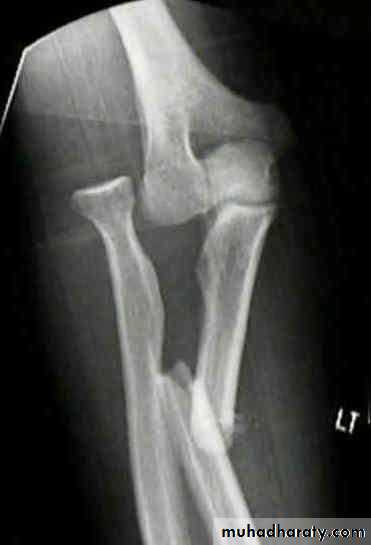

X-ray

With isolated fractures of the ulna, it is essential to obtain a true anteroposterior and true lateral view of the elbow. In the usual case, the head of the radius (which normally points directly to the capitulum) is dislocated forwards, and there is a fracture of the upper third of the ulna with forward bowing.